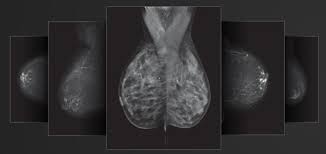

Densitas Announces the Commercial Release of intelliMaven: The First GPT AI Companion to Elevate Mammography Quality Standards